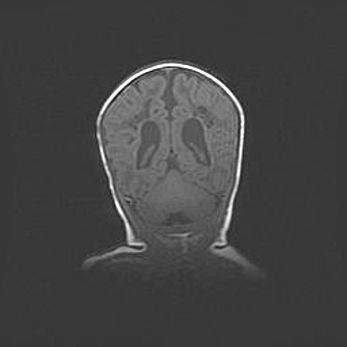

Сообщающаяся гидроцефалия. Кистозная энцефаломаляция головного мозга.

Возраст: 3 месяца 4 дня

Вес: 3100 г

Пол: женский

Окружность головы: 34 см

Срок гестации: 31 неделя

Кистозная энцефаломаляция головного мозга - одна из форм поражения головного мозга в детском возрасте. Характеризуется возникновением множественных и распространённых кист в коре, белом веществе и подкорковых образованиях головного мозга у плодов, новорождённых и детей раннего возраста. Развитие кистозной энцефаломаляции связано с внутриутробной асфиксией и гипотонией, родовой травмой, тромбозом синусов, пороками развития сосудов, инфекциями, сепсисом и другими причинами. Наиболее значимые инфекционные агенты: вирусы простого герпеса, цитомегалии, краснухи, токсоплазмы, энтеробактерии, золотистый стафилококк и другие.